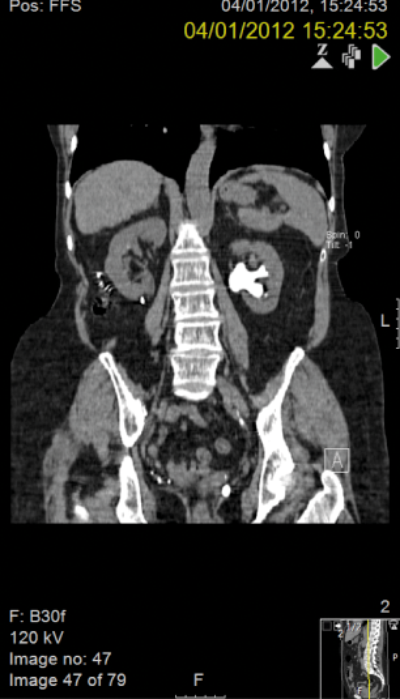

A 37-year-old male presented with stones in a right pelvic kidney. Flexible ureteroscopy demonstrated a tight and very tortuous ureter with no access to the renal pelvis.

PCNL was discussed at a specialist x-ray meeting but considered unsafe due to the risk of perforating overlying bowel.

A right sided transperitoneal laparoscopic approach was utilised, sweeping ascending colon medially. The renal pelvis was incised and stones were removed using a flexible cystoscope and the renal pelvis was closed over a stent.

At three years postoperatively, the patient was asymptomatic with stable renographic function and stone-free.

Figures above demonstrate worsening hydronephrosis preoperatively.

The patient postoperatively.